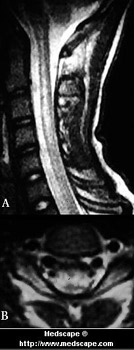

Figure 3. Spinal cord DCS (cervical tract). Reprinted from the Journal of Magnetic Resonance Materials in Physics, Biology and Medicine. Malattia da decompressione del tratto cervicale del midollo spinale